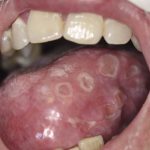

Афтозный стоматит (фото 2) сопровождается возникновением во рту так называемых афт или эрозий. Процесс этот очень неприятный, больные испытывают характерное жжение. Недуг также осложняет прием пищи. Могут отмечаться гипертермия и местный лимфоаденит. Не вылеченный афтозный стоматит может перейти в хроническую форму. Более подробно читайте в статье афтозный стоматит на нашем сайте.